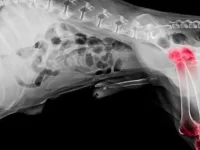

高尿酸血症:这是动物体内最终产生过多尿酸的一种情况。尿酸过多意味着肾结石、膀胱结石,甚至痛风。这种情况在公狗中比母狗更常见。